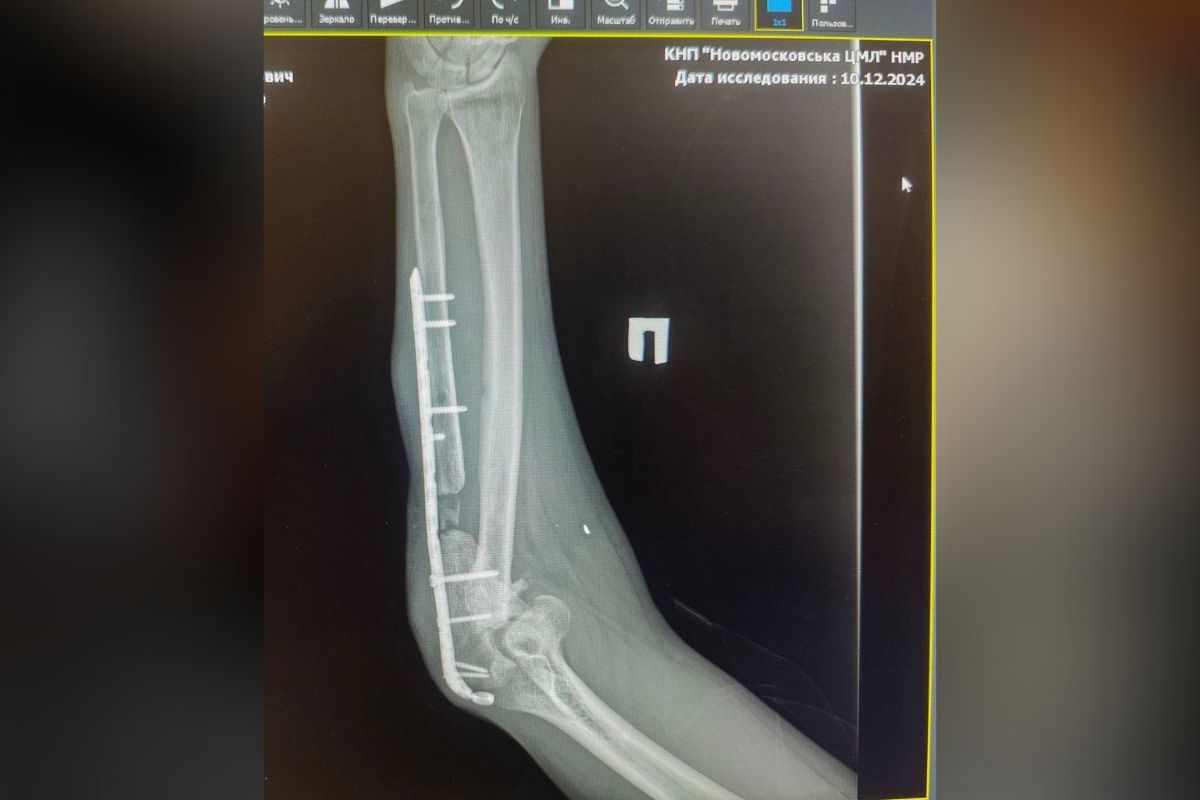

Однако при попытке полицейскими надеть на ветерана наручники, тот начал громко кричать, что у него сломана рука, и в ней пластина.

Позже в неофициальном канале 25-й бригады появились фото рентген руки бойца, на лечение которой собирали средства. Телеграмм-канал "Днепр Сейчас" публиковал видео, как «Ямаха» проходил реабилитацию после получения тяжелых ранений на передовой, где ему раздробило руку.